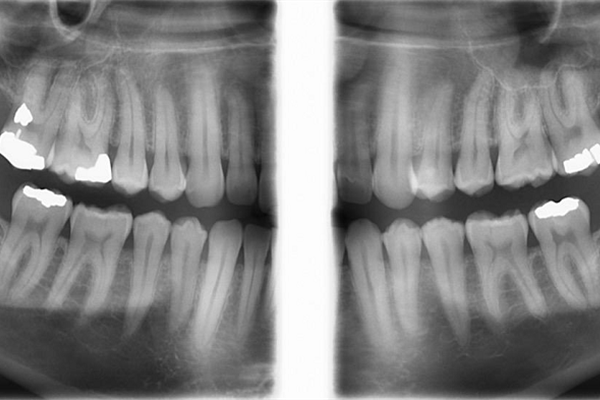

در این تکنیک رادیوگرافی بایت وینگ بدون قرار دادن گیرنده یا وسیله دیگری در داخل دهان، تهیه میشود. کودکان اغلب از جایگزاری گیرنده های رادیوگرافی در داخل دهان امتناع میورزند و تصویرداریهای داخل دهانی برای کودکان اغلب امری ناخوشایند است. بدین منظور، تهیه رادیوگرافی بایت وینگ که از کلیشه های مهم تصویربرداری کودکان میباشد، در این مرکز صورت خارج دهانی قابل انجام است. این تکنیک همچنین میتواند جایگزین مناسبی برای بایت وینگ داخل دهانی در افراد بزرگسالی باشد که به دلیل تهوع شدید، امکان تحمل گیرنده را در داخل دهان خود ندارند. لازم به ذکر است بالاترین رزولوشن و وضوح تصویر در رادیوگرافی های داخل دهانی مشاهده می شود.